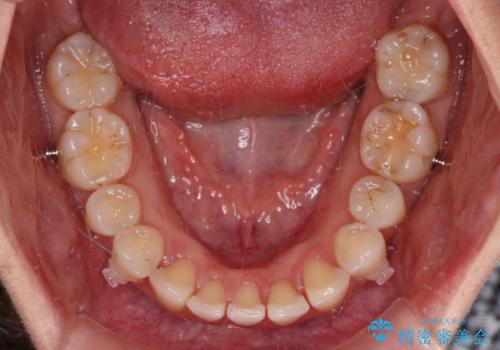

- 矯正装置

- インビザライン

- 治療期間

- 1年6ヶ月

親知らずを抜去し、歯列全体を後方に移動させつつ、IPR(歯と歯の間を削る)でスペースを獲得し、インビザラインを用いて叢生を解消しながら前歯の突出を改善することとしました。